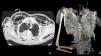

Iatrogenic tracheal rupture (ITR) is a serious complication secondary to procedures such as emergent orotracheal intubation or tracheostomy, among others. The management of ITR depends on the size, extension and location of the injury, along with the patient's respiratory status and comorbidities. The priority of treatment is to keep the airway permeable to ensure adequate ventilation. We present the case of a tracheal rupture after performing a percutaneous tracheostomy, in a patient diagnosed with severe acute respiratory distress syndrome secondary to bilateral interstitial pneumonia due to SARS-Cov-2. The issues are discussed, such as the management (conservative vs. surgical) depending on the features of the injury and the patient, in the extraordinary context that the COVID-19 pandemic has entailed.